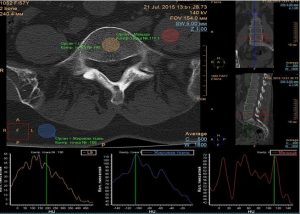

Компьютерная томография (КТ) с денситометрией костей основана на измерении абсорбции рентгеновских лучей костной тканью. Процедура проводится на обычном КТ-сканере, который измеряет количество пройденного через кости излучения. Результаты выражаются в единицах Hounsfield (HU), и чем выше значение HU, тем плотнее кость.

КТ-денситометрия часто используется для исследования вертебральных тел позвоночника, особенно в случаях подозрения на переломы из-за остеопороза.